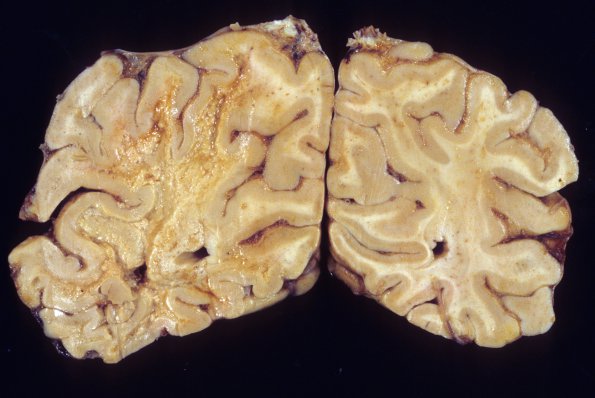

Washington University Experience | INFECTION | Viruses | PML (JC Virus) | PML - Gross Pathology | 3A1 PML (Case 3) 4

3A1,2 In this case the white matter degeneration is severe with granular disintegration, discoloration and cavitation.